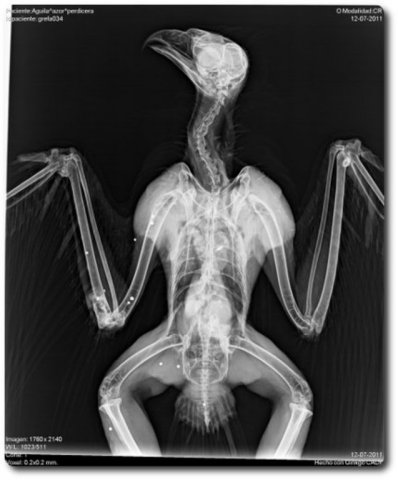

Radiografía de un águila disparada

Detalle